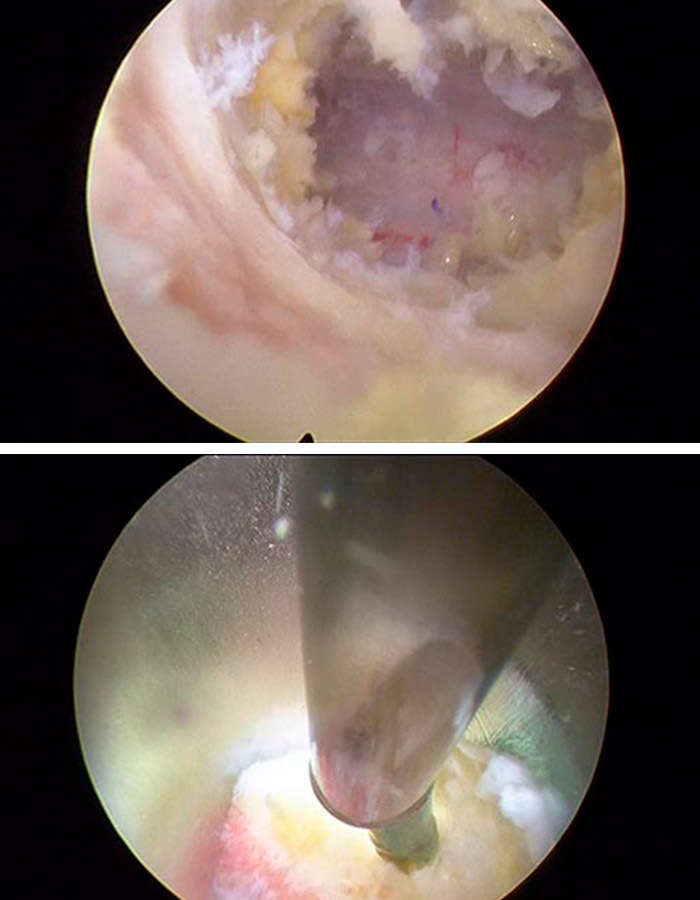

Para poder efectuar la operación, realizamos un abordaje inter-laminar posterior con una aguja guía y dentro un dilatador que nos permite no dañar ningún tejido neurológico, muscular u óseo y acceder directamente a la zona en la que vamos a trabajar.

Procedemos a la liberar de la estenosis el canal con mucha delicadeza y revisando que no quede ningún resto, todo ello mediante una incisión cutánea de 3mm muy precisa.

Tras realizar este vaciado comprobamos cómo queda adecuadamente liberadas las estructuras neurológicas vigilando que el espacio que queda ahora sea el correcto.